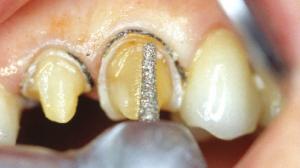

Une préparation coronaire périphérique a déjà été réalisée sur la 22.

Préparation de la 23. Réalisation d'un sillon qui suit le périmètre de la face vestibulaire avec une fraise boule de 1mm.

La fraise boule est enfoncée à moitié. Ce sillon aura donc une profondeur d’environ 0,5 mm. Au collet, le sillon est pour le moment nettement éloigné de la gencive.